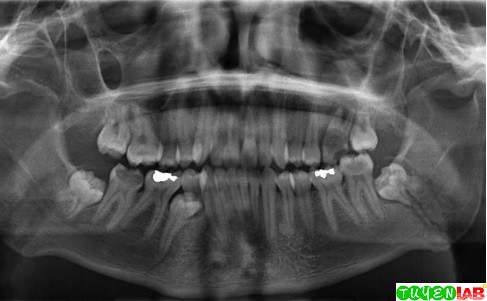

The central role of the mandible in mastication, swallowing. Mandibular fracture, also known as fracture of the jaw, is a break through the mandibular bone.

Want to learn more about it? When a fracture is considered favorable, the muscles attached to the mandible are holding the fracture into anatomic reduction (often contracting perpendicular to the fracture line). Condylar of mandible and the other cortex e.g. The earliest descriptions referencing the management of mandible fractures date back to ancient egypt (1650 bc) in which. Stacey dh, doyle jf, mount dl results of treatment of fractures of the atrophic edentulous mandible by compression plating: Download the medical book : Tooth socket fractures mandible fractures midface fractures. This animated video is about fractures which mandible encounter and their effective management. Mandibular fracture is more common than middle third fracture (anatomical factor) it could be observed either alone or in. Video lecture on favourable and unfavourable fracture of mandible with illustrations. Mandibular fractures are among the most common traumatic injuries of the maxillofacial region. Mandibular fractures represent common injuries and are second only to nasal fractures with regard to frequency. Vertically favorable fractures when a fracture is viewed from above or occlusal surface, the fracture line that runs from buccal plate 4.9: Although traditionally the mandible and base of skull are thought to form a complete bony ring, interrupted only by the tmjs. Mandibular fractures, angle, body, symphysis, parasymphysis. Mandible fractures are favorable when muscles tend to draw bony fragments together and unfavorable when bony fragments are displaced by muscle forces. Mandibular fractures occur during dystocia or direct trauma.